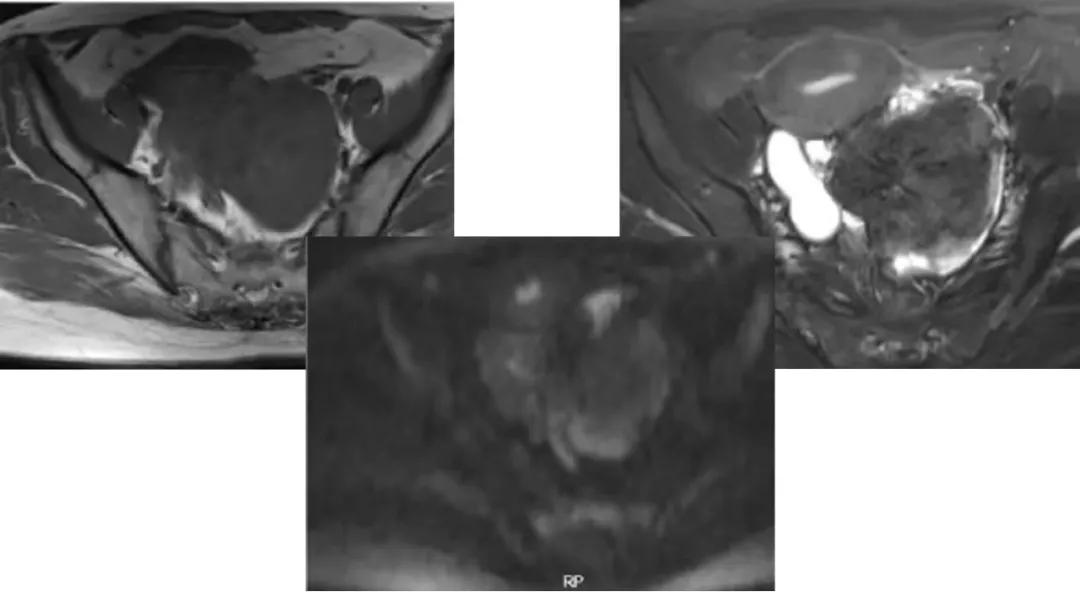

病理:卵巢子宫内膜样癌

病例4 女,32岁,以“月经量增多伴经期延长半年。”

缘于患者入院前半年无明显诱因出现月经量增多,卫生巾由原来3包余增至5包不等,伴血块,经期由原来7天延长至10-15天不等,无痛经,无月经周期改变,无阴道异常排液,无畏冷、发热,无头晕、乏力等不适,未重视,未诊治。期间症状持续。2月前就诊我院,查彩超示:“子宫体大小约5.7*5.3*4.6cm,内膜厚约0.6cm,回声不均,左卵巢旁探及大小约4.2*3.5cm低回声区。”建议治疗,患者及家属表示考虑。期间症状持续,今就诊我科门诊,要求住院手术治疗,无腹痛等不适,门诊拟“卵巢囊肿”收住入院。既往史:2007年剖宫产一次,术顺。月经史:15 7/25 lmp2018.05.14,量中,无痛经。婚育史:已婚,1-0-3-1,末孕2007年剖宫产娩一男婴,儿子及丈夫体健。个人史、家族史均无特殊。

CA125 335.5(U/mL);2018-05-30 彩超:子宫宫体大小约5.6㎝×6.3㎝×4.9㎝,形态正常,宫壁回声欠均,内膜厚约1.8cm,回声不均。CDFI:子宫内未见明显异常彩色血流信号。左附件区探及一混合回声团块,大小约9.8㎝×7.9㎝,CDFI:其实性部分可见少许彩色血流信号。右附件区未见明显包块回声。